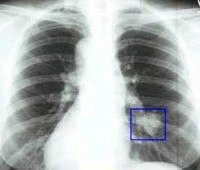

Выраженные физикальные проявления на ранних этапах онкопроцесса в легких нехарактерны. Основным источником выявления злокачественных опухолей легких на стадии отсутствия клиники является рентгенография. Злокачественные опухоли легких могут быть случайно выявлены при проведении профилактической флюорографии. При рентгенографии легких определяются опухоли диаметром более 5-6 участки сужения и неровностей контуров бронхов, ателектаза и инфильтрации. В сложных диагностических случаях дополнительно проводят МРТ или КТ легких.